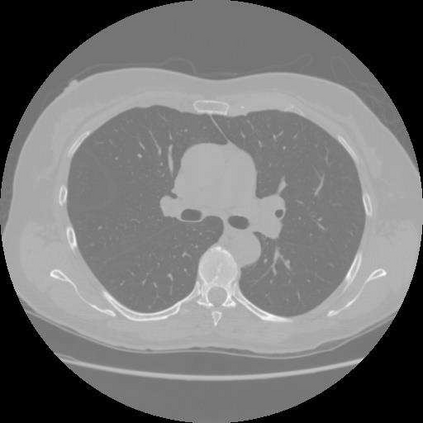

Sparse-view computed tomography (CT) is known as a widely used approach to reduce radiation dose while accelerating imaging through lowered projection views and correlated calculations. However, its severe imaging noise and streaking artifacts turn out to be a major issue in the low dose protocol. In this paper, we propose a dual-domain deep learning-based method that breaks through the limitations of currently prevailing algorithms that merely process single image slices. Since the scanned object usually contains a high degree of spatial continuity, the obtained consecutive imaging slices embody rich information that is largely unexplored. Therefore, we establish a cascade model named LS-AAE which aims to tackle the above problem. In addition, in order to adapt to the social trend of lightweight medical care, our model adopts the inverted residual with linear bottleneck in the module design to make it mobile and lightweight (reduce model parameters to one-eighth of its original) without sacrificing its performance. In our experiments, sparse sampling is conducted at intervals of 4{\deg}, 8{\deg} and 16{\deg}, which appears to be a challenging sparsity that few scholars have attempted before. Nevertheless, our method still exhibits its robustness and achieves the state-of-the-art performance by reaching the PSNR of 40.305 and the SSIM of 0.948, while ensuring high model mobility. Particularly, it still exceeds other current methods when the sampling rate is one-fourth of them, thereby demonstrating its remarkable superiority.